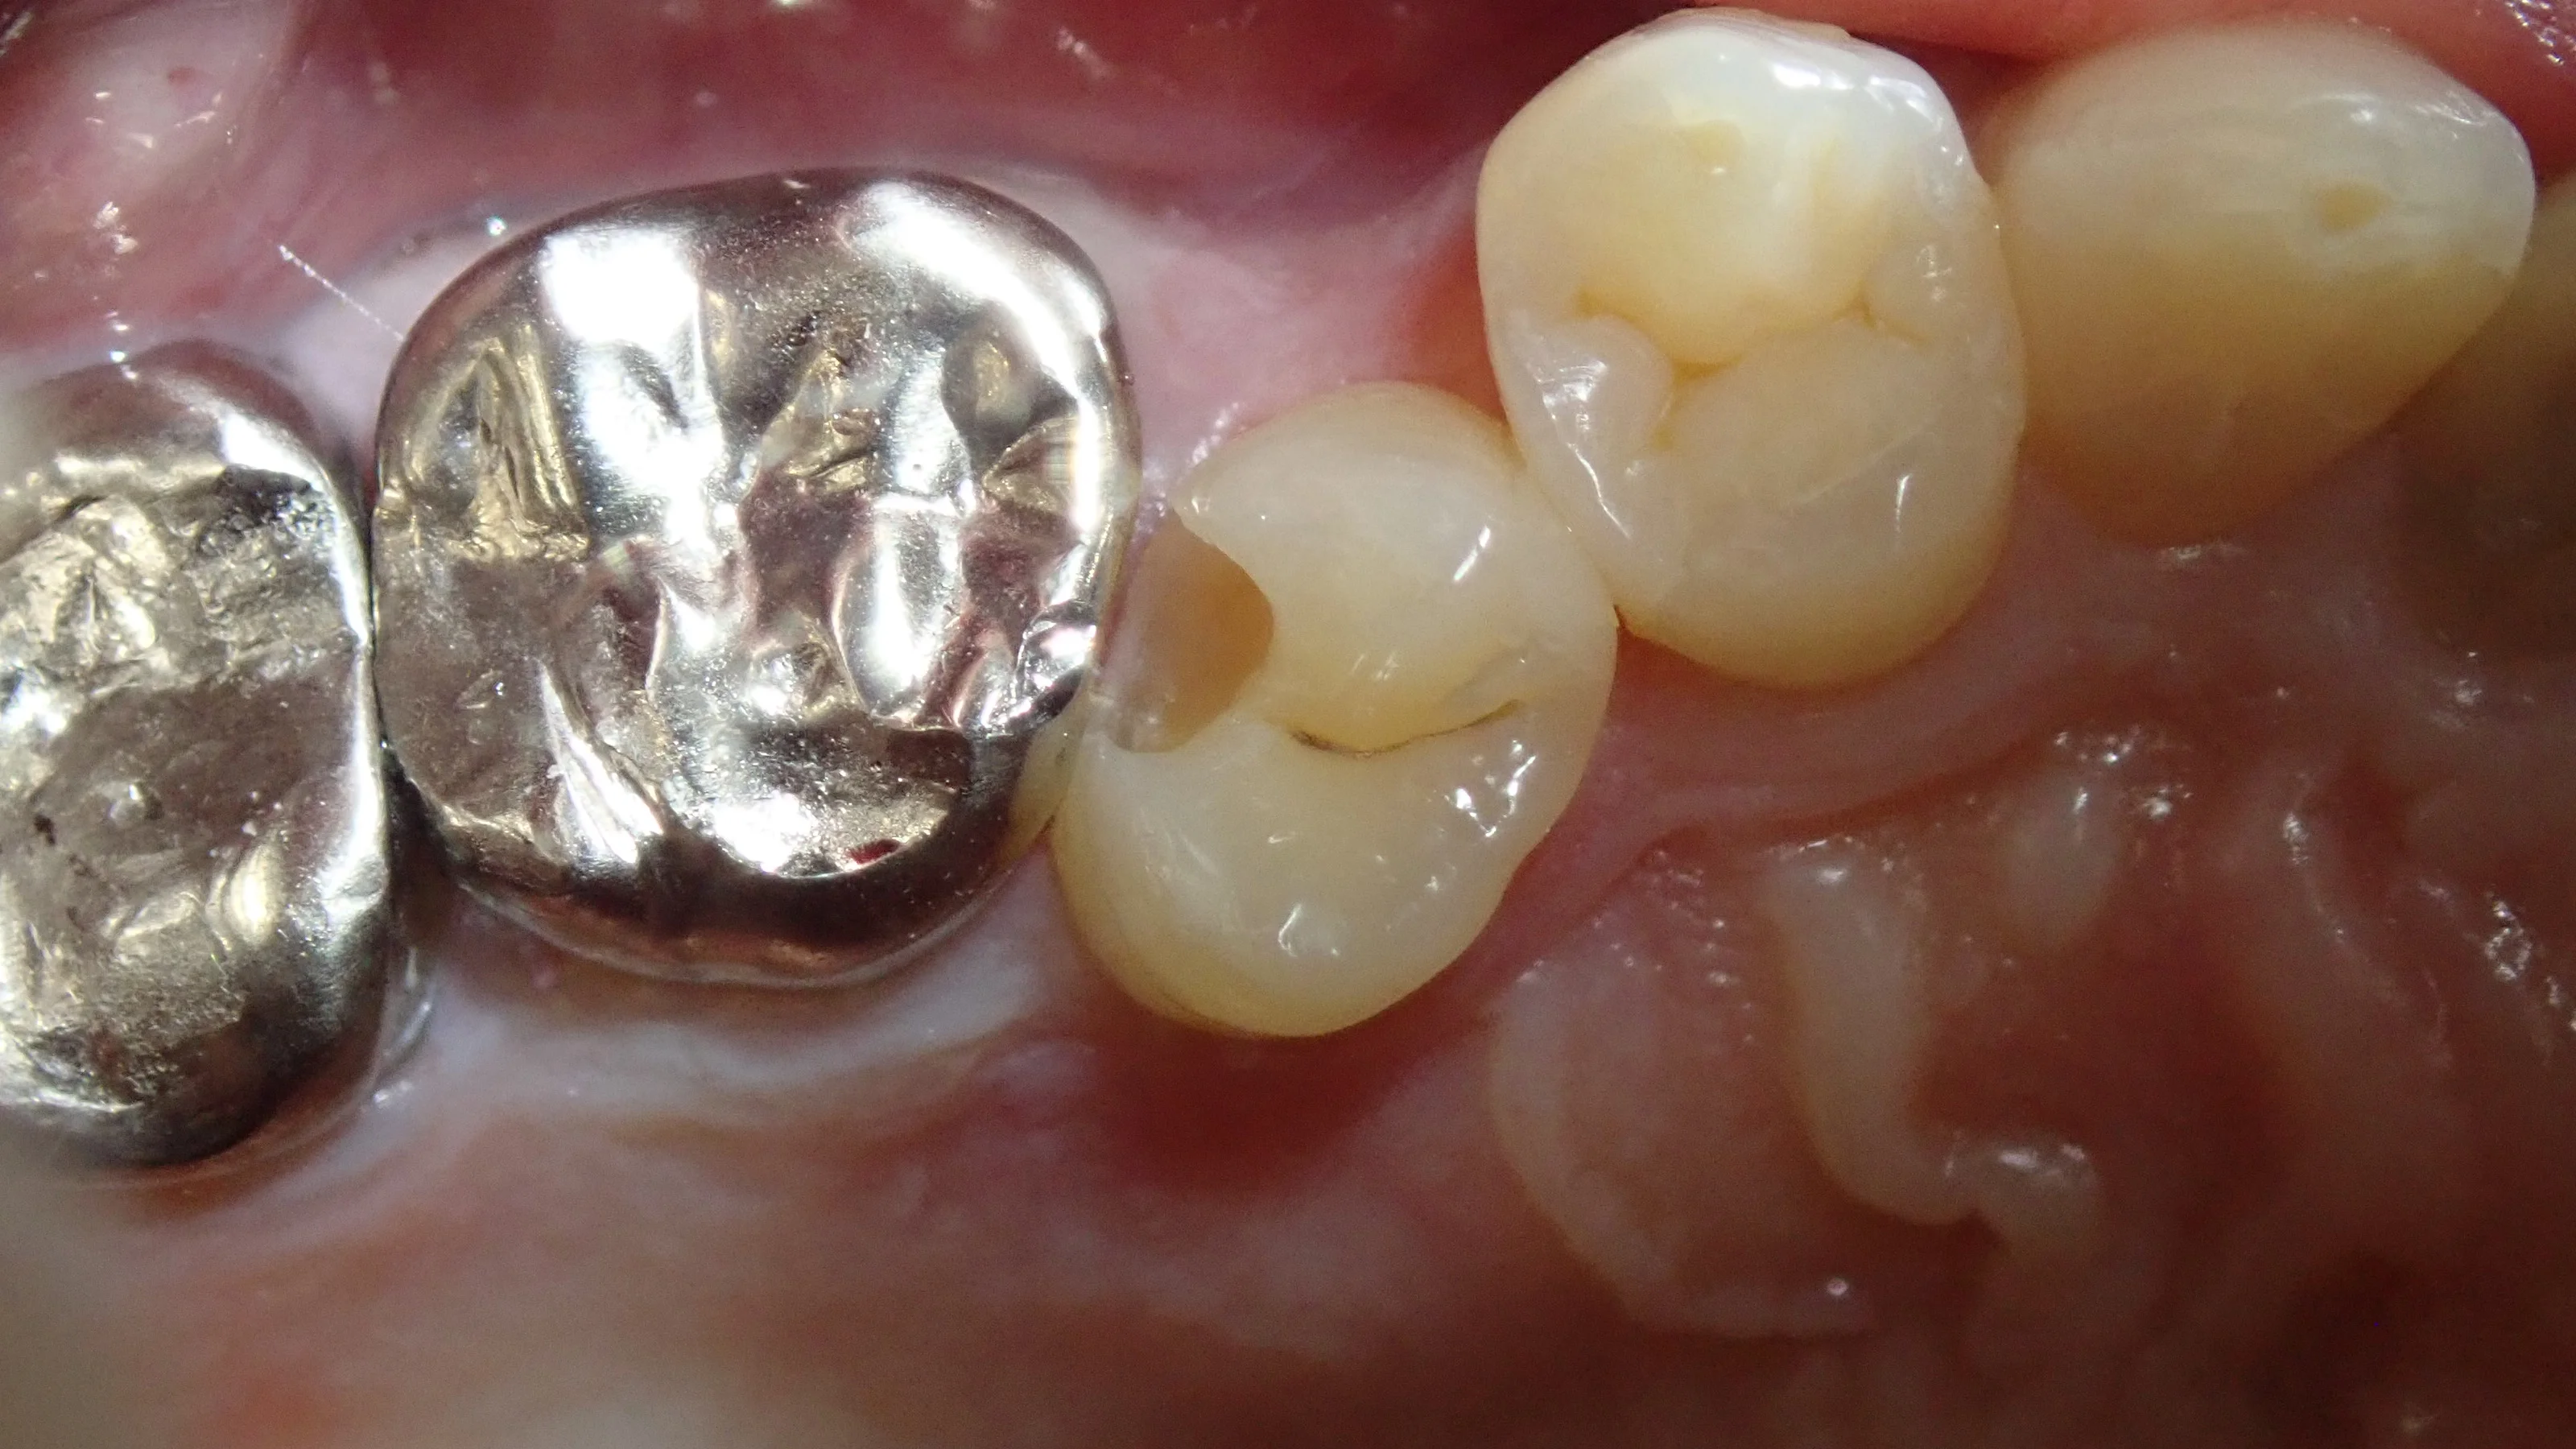

この日の術前術後がこちらです。

で、2日目最終的な術前術後がこちらです。

歯の乾燥の為、まだ色が合っていませんが、1週間くらいすると馴染んできます。

無事に虫歯も取りきり、段差などなく仕上げることが出来たため、良かったです。